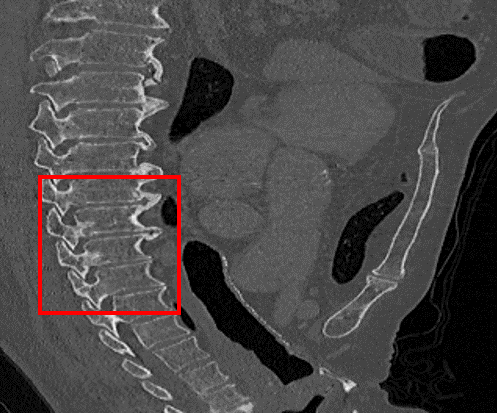

Figure 7: Visual comparisons of different methods against SAINT. The difference maps are provided to the right of the results for better visualization. Images are best viewed when magnified.

In this section, we evaluate the performance of our method and other SISR approaches. Quantitative comparisons are presented in Table 2. MDCSRN uses a DenseNet structure with batch normalization, which has been shown to adversely affect performance in super-resolution tasks [17, 27]. Furthermore, inference with 3D patches lead to observable artifacts where the patches are stitched together, as shown in the mDCSRN results in Fig. 7.

For liver, colon and hepatic vessels datasets, SAINT drastically outperforms the competing methods; however, the increase in performance is less significant with the kidney dataset. Generalizing over unseen dataset is a challenging problem for all data-driven methods, as factors such as acquisition machines, acquisition parameters, etc. subtly change the data distribution. Furthermore, quantitative measurements such as PSNR and SSIM do not always measure image quality well.

We visually inspect the results and find that SAINT generates richer detail when compared to other methods. It is evident in Fig. 7 that there is a least amount of structural artifacts remaining in the different images produced by SAINT. For more discussion on SAINT’s advantage in resolving the memory bottleneck and more slice interpolation results, please refer to the supplemental material section.